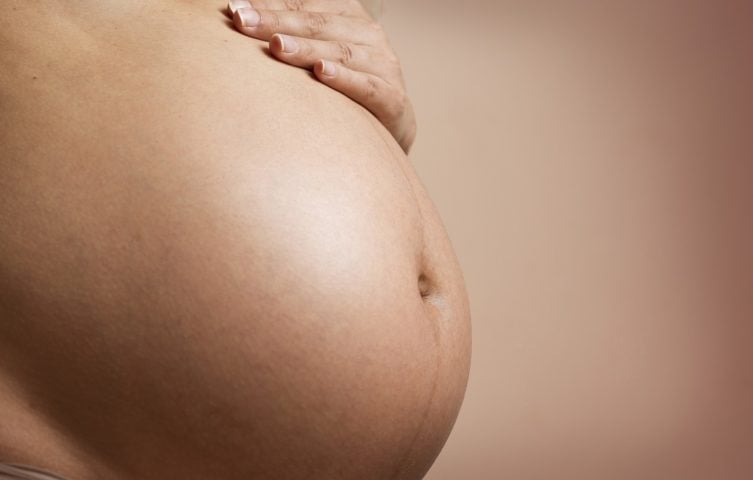

Mulher passa mais de 50 anos com feto calcificado na barriga